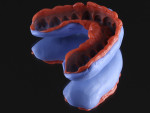

A second workflow will be used to reconstruct a dental arch following the esthetic canons of Mayan dentistry. As in the first workflow, the initial step requires an acquisition. An intraoral scanner (CEREC®, Dentsply Sirona, dentsplysirona.com) is used to record the maxillary arch in all its details. Since a recent update, the software (CEREC SW 4.5) associated with the intraoral scanner makes it easy to export the scan in STL format to be printed in 3D (Figure 7). After a base for the dental model is created with a 3D modeling software, the STL file is sent to the 3D printer (Solflex 170, Voco). The model is printed (V-Print model, Voco) in a shade close to A2 (VITA North America, vitanorthamerica.com) (Figure 8).

To achieve a wax-up that is as natural looking as possible, a digital smile design (DSD)14 is performed beforehand. The incisors are modified according to a Mayan pattern: The lateral incisors undergo a horizontal incisal reduction, while the central incisors are altered to create a mesial step. The incisors and canines receive a spherical inlay in the buccal aspect (Figure 9). The inlays may either be completely flat in the continuity of the buccal surface, form a spherical outgrowth while remaining within the confines of the cavity, or form a spherical outgrowth that exceeds the limits of the cavity.2

Following the DSD, characterization is created with fluid composite (Admira Fusion, Voco), with more chromatic shades used for the posterior teeth (A3.5 for the molars, A3 for the premolars) and less chromatic shades for the anterior teeth (A2 for the canines, A1 for the incisors). Composite tints (FinalTouch, Voco) are used in the grooves and embrasures. The gingiva is reproduced with a pink composite (Amaris Gingiva, Voco). Finally, the gemstone inlays are made of colored composite (Twinky Star, Voco) in green to imitate jade and blue to imitate turquoise. The final result is a dental arch that gives the realistic impression of a Mayan dentition with natural flaws and uncanny beauty (Figure 10).

Today's composites may be used to effectively recreate quite realistic results, giving clinicians the means to design smiles that patients often strongly desire. These effectual results can be achieved in a predictable and esthetic way.